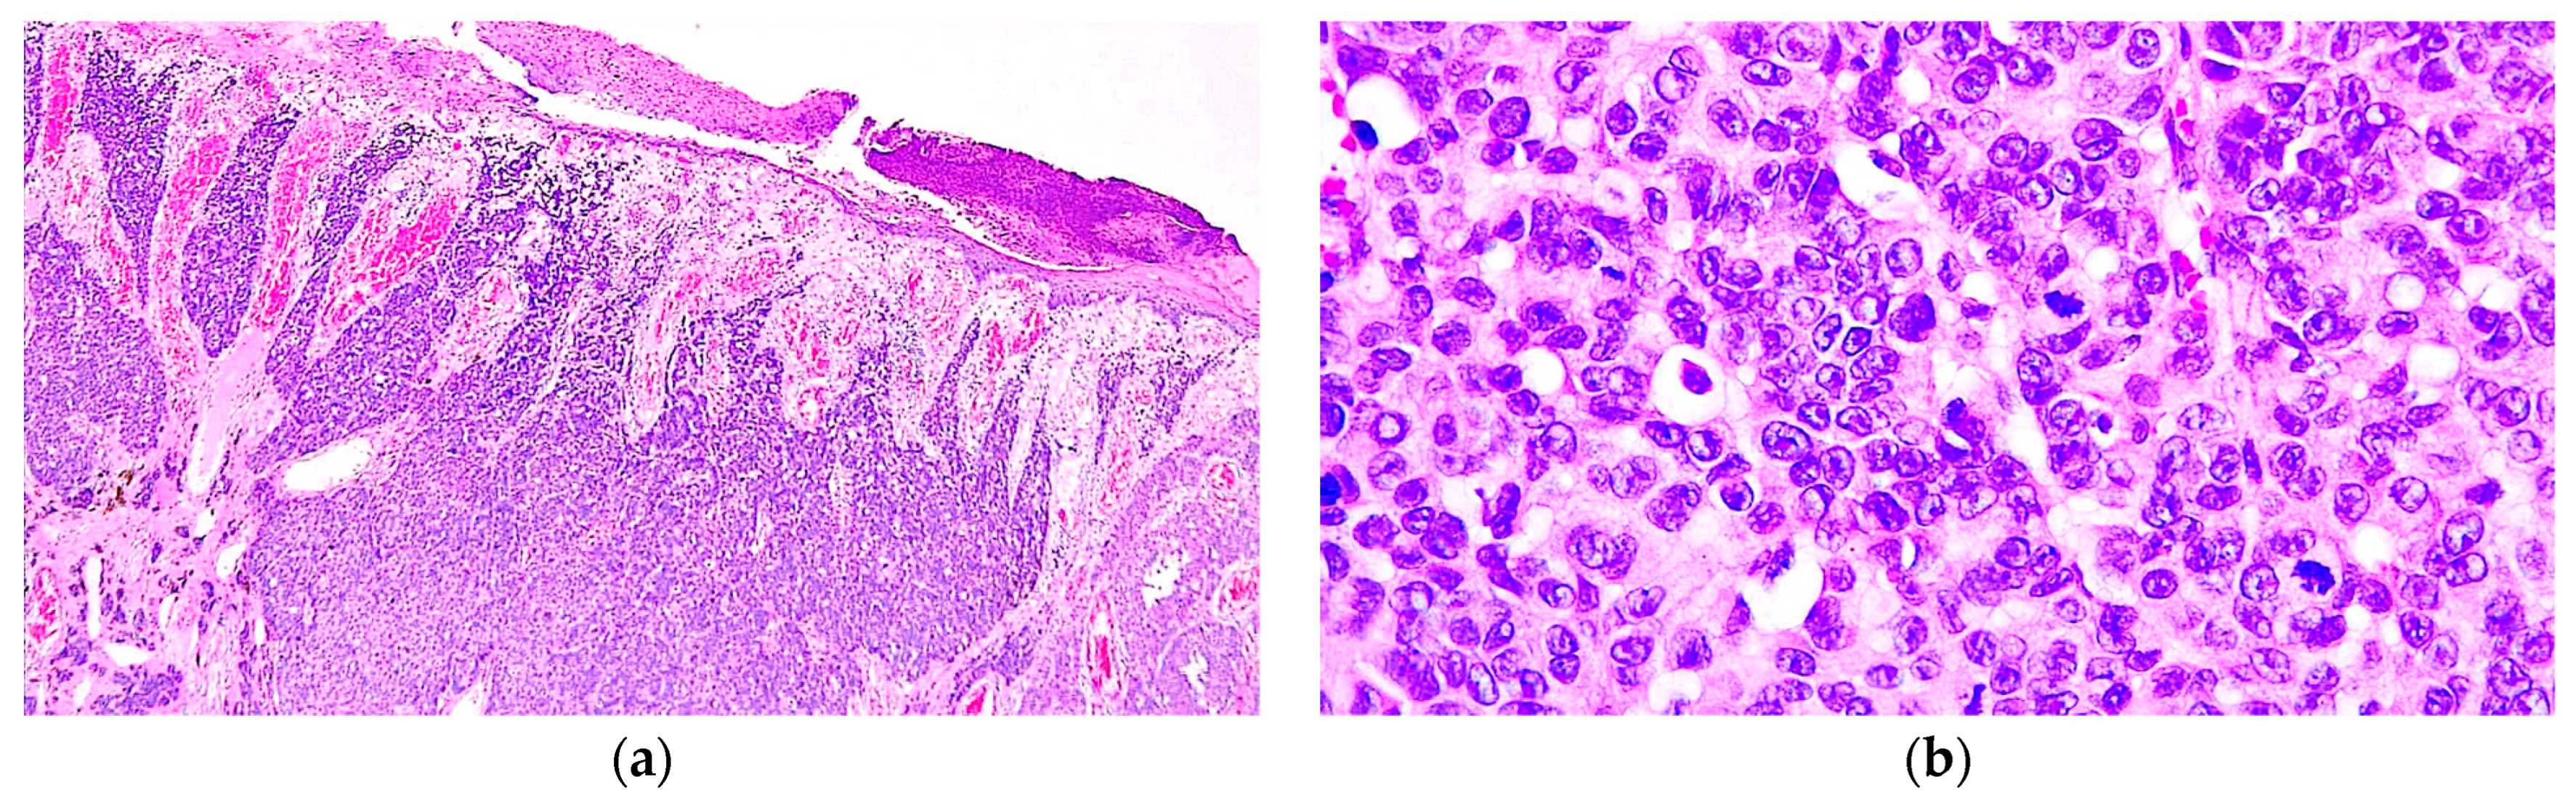

Metastatic Nodular Melanoma with Angiosarcomatous Transdifferentiation—A Case Report and Review of the Literature

- Kilsdonk, M.J.; Romeijn, T.R.; Kelder, W.; van Kempen, L.C.; Diercks, G.F. Angiosarcomatous transdifferentiation of metastatic melanoma. J. Cutan. Pathol. 2020, 47, 1211–1214. [Google Scholar] [CrossRef] [PubMed]